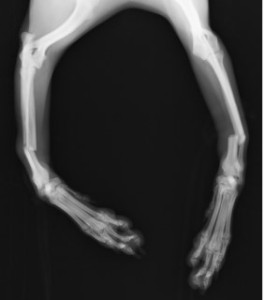

手術前